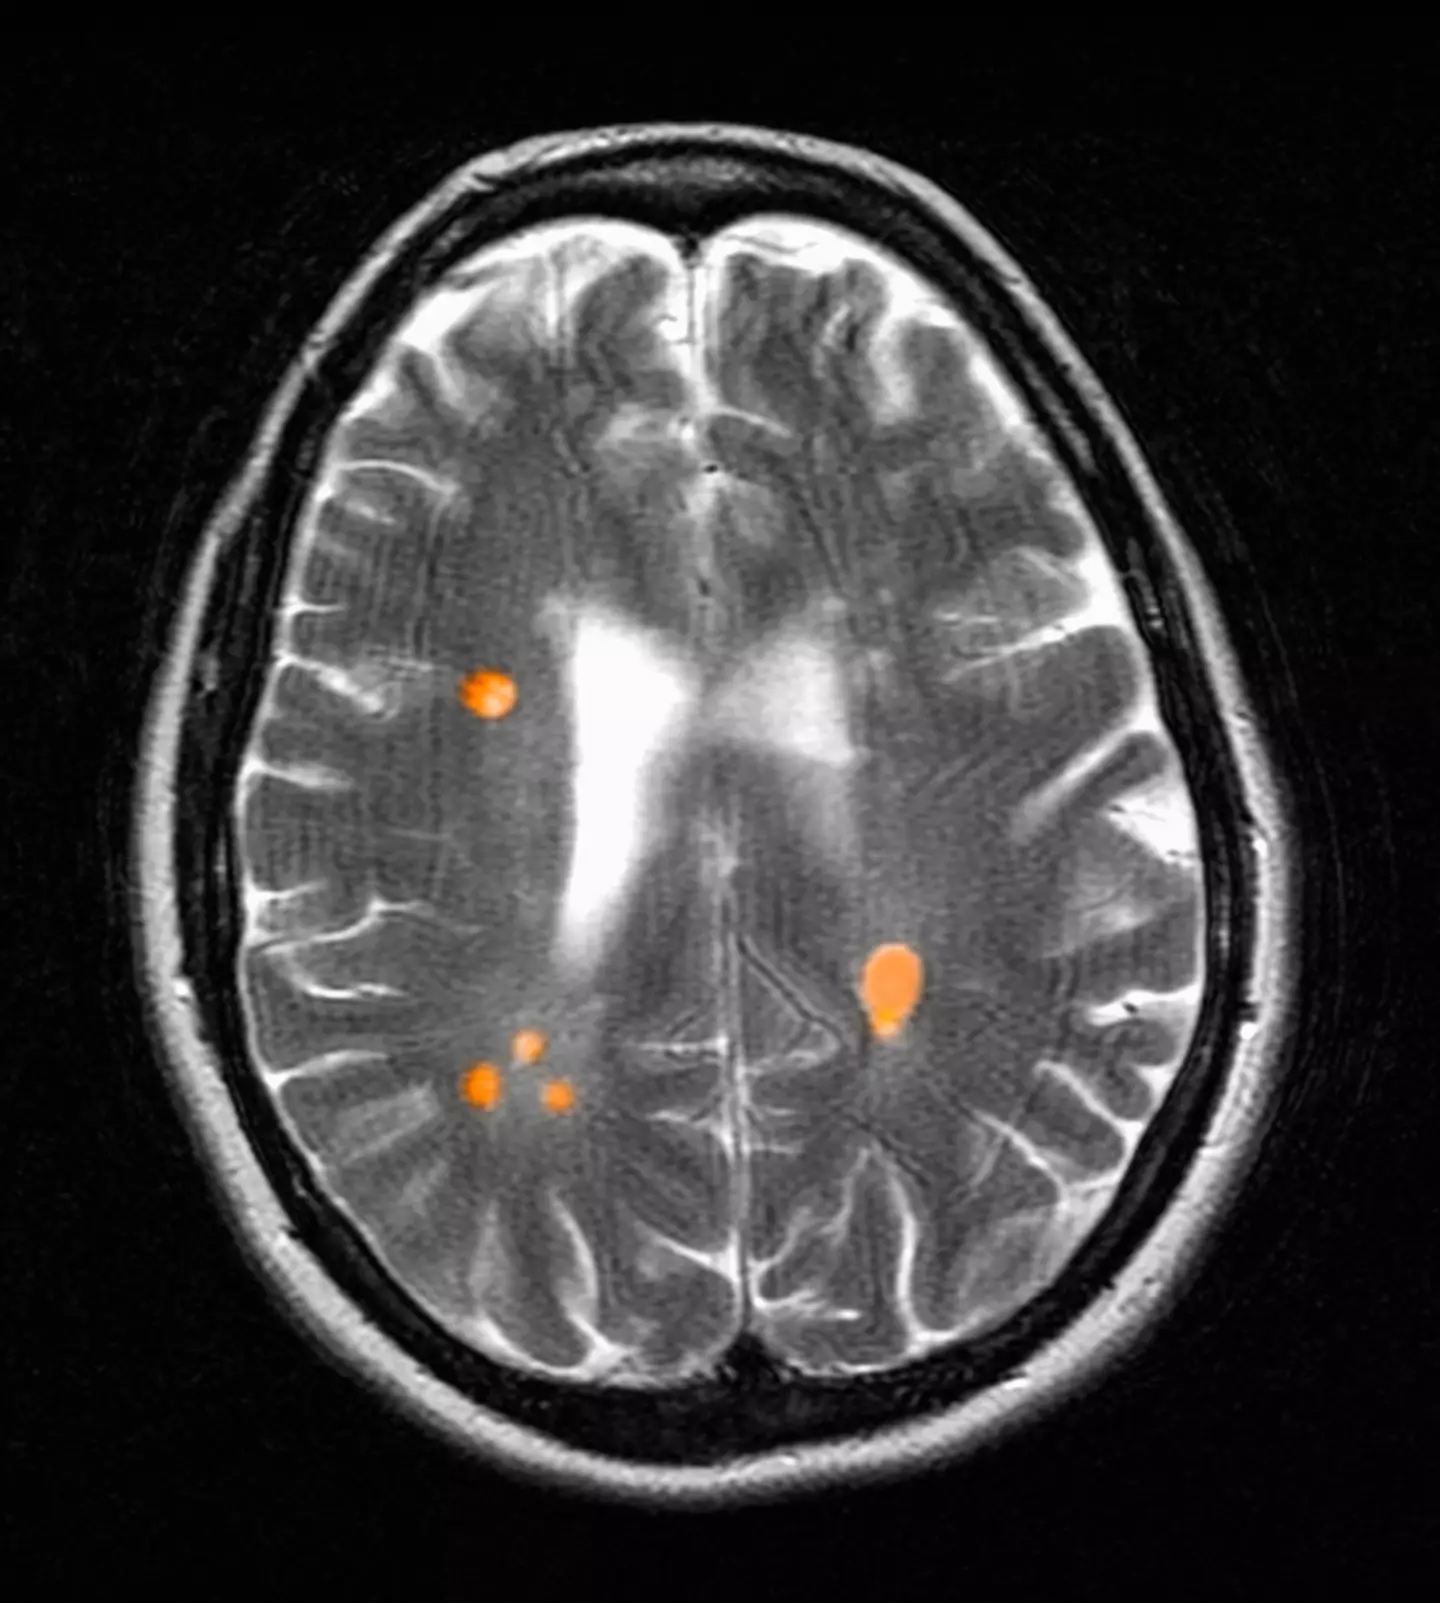

MS is a lifelong condition which affects both the brain and spinal cord, causing a wide range of varying symptoms including problems with vision, arm or leg movement, sensation or balance, muscle stiffness, numbness and problems with thinking, learning and planning.

"In people who have multiple sclerosis, it is most important to look for signs of a new inflammatory relapse," Dr. Paige Sutton, a neurologist specialising in neuroimmunology and multiple sclerosis for OhioHealth, told Healthline.

"Relapses are typically very obvious and would include new neurologic symptoms that are constant and last for more than 24 hours."